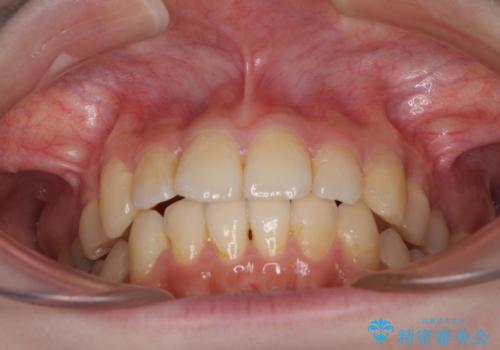

デコボコ歯列をきれいに インビザラインによる矯正治療

- 2年8ヶ月

- 上下歯列全体のデコボコを気にして来院された患者様です。

主に下顎歯列全体の後方移動とIPR(歯と歯の間を削る)によってデコボコが解消するように設計し、インビザラインにより治療を行うこととしました。

奥歯の知覚過敏が顕著となり、その影響で奥歯の咬み合わせ改善のための顎間ゴムの装着ができず、咬合を仕上げるまでに長い期間を要することとなりました。